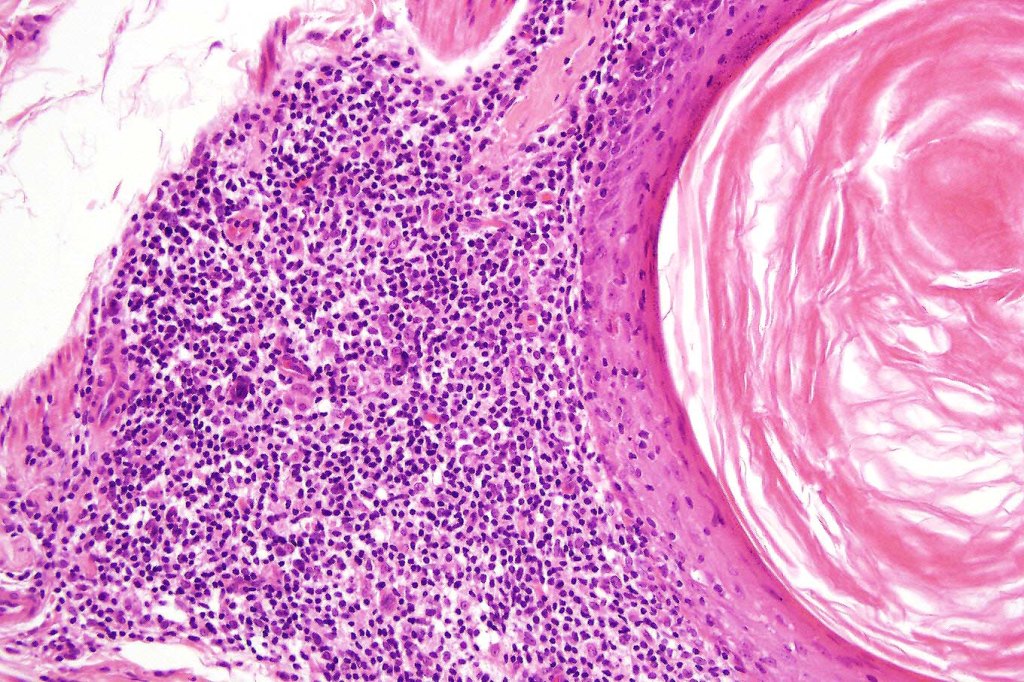

Histological features

•Follicular infiltration by atypical lymphocytes & Sézary cells

•Eosinophils sometimes conspicuous (eosinophilic folliculitis-like appearance)

•Granulomatous inflammation secondary to follicular destruction